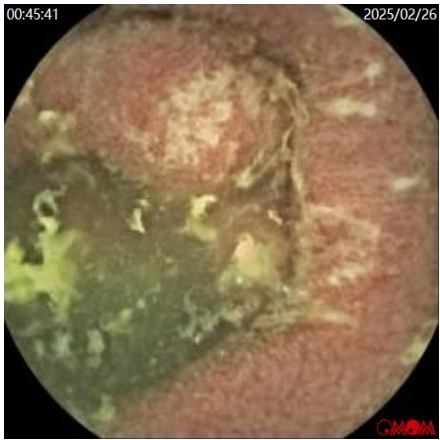

胶囊内镜(图5

小肠多发溃疡、糜烂:小肠淋巴管扩张?

图5a  胶囊内镜示小肠见白色绒毛样改变,小肠糜烂

图5b  胶囊内镜示小肠阿弗他样溃疡